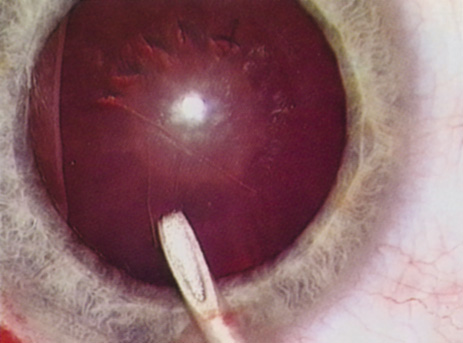

HYDRODISSECTION

Hydrodissection can be performed after the surgeon has successfully completed capsulorrhexis.97 If the capsulorrhexis is not intact, fluid forced around the interior of the capsule may cause the bag to splay open. With capsulorrhexis, hydrodissection is a safe and extremely useful maneuver. Hydrodissection can be thought of as two maneuvers: hydrodelineation and cortical cleaving hydrodissection. By placing a 27-gauge cannula on a syringe filled with balanced saline solution (BSS), the surgeon can direct fluid beneath the residual anterior capsular rim to create a cleavage plane. Depending on the direction the fluid wave takes, different lamellae of the cataract will be separated. Hydrodelineation is the term used when the cleavage plane separates the adult nucleus from the fetal nucleus or the adult nucleus from the more peripheral epinucleus. Hydrodelineation often results in the characteristic golden ring sign (Fig. 11). Cortical cleavage occurs when the cortex is separated from the capsular bag (Fig. 12). Finding the cortical cleavage plane may be facilitated by gently lifting the capsular margin away from the cortex with the BSS cannula before injecting. Several small bursts of fluid allow the surgeon to monitor progress of the fluid wave. When dealing with a soft nucleus, the authors strive to perform true cortical cleaving hydrodissection. For a hard nucleus, hydrodelineation allows manipulation of less of the nuclear bulk, although the remaining epinuclear shell must be addressed in an additional step. Hydrodelineation is particularly useful if the nucleus is not freely mobile after cortical cleaving hydrodissection.

Fig. 11. A crisp “golden ring” is seen from the fluid cleft between the epinucleus and nucleus with hydrodelineation.

Fig. 12. Hydrodissection, performed subincisionally with a 27-gauge J-cannula, produces a cleavage plane between the capsule and the cortex. The small blue arrows indicate the advancing fluid wave.